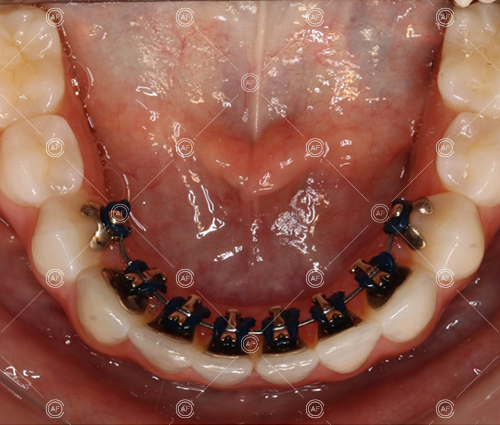

Treatment progressed by starting with thin, flexible nickel titanium archwires of a round diameter, transitioning to a rectangular nickel titanium archwire before eventually working up to a working archwire (1925 stainless steel).

Residual space from the extractions were closed using upper and lower nickel titanium closing coils. Class 2 elastics were used to facilitate space closure in order to gain class 1 buccal segments.